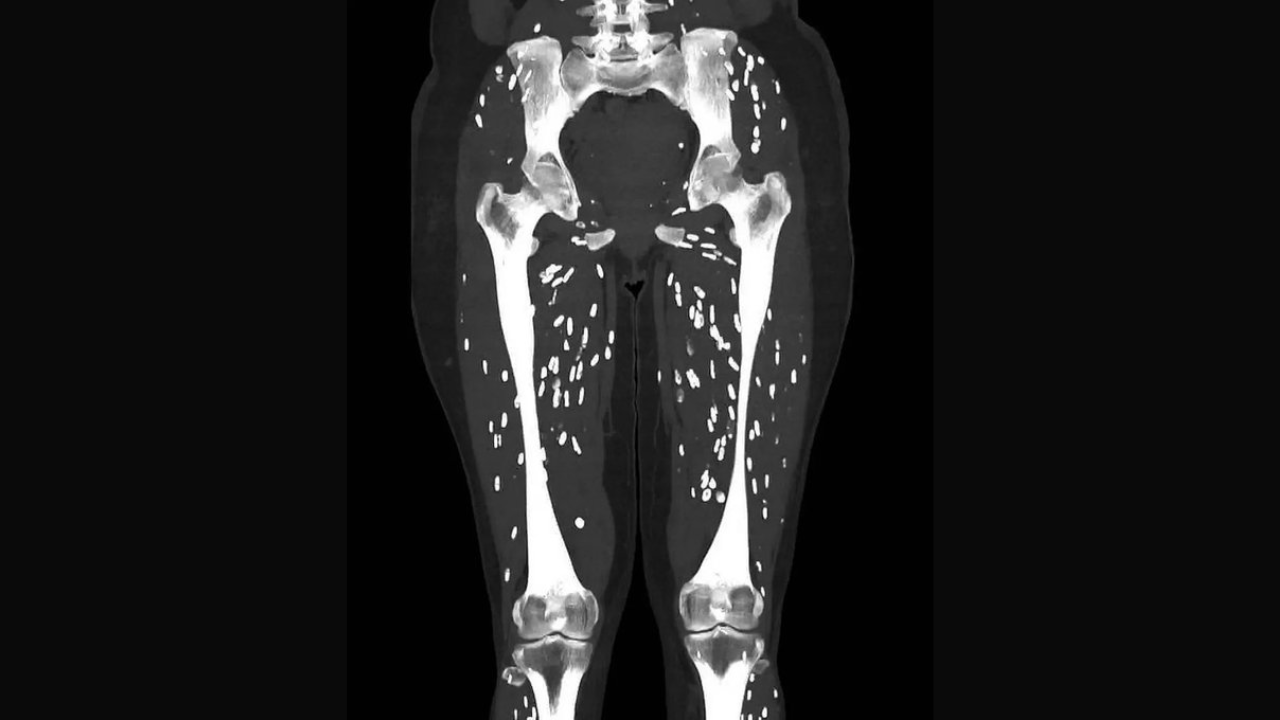

The CT scan image of a patient is going viral over the internet. In the image we see tiny spots in the legs of the individual and you would be shocked to know that these tiny spots are the tapeworm cysts.

The image has been shared by Sam Ghali on X (formerly Twitter). "Here’s one of the craziest CT scans I’ve ever seen, What’s the diagnosis?," he captioned the picture.

In subsequent posts made on X, he has explained that it is a condition called cysticercosis which is caused when one consumes larval cysts of Taenia Solium or tapeworm.

"The hosts inflammatory response typically ends up killing off the cysts, which subsequently undergo calcification, giving them the classic appearance you can appreciate on this CT scan. These are commonly referred to as “rice grain calcifications”, Sam Ghali explains.